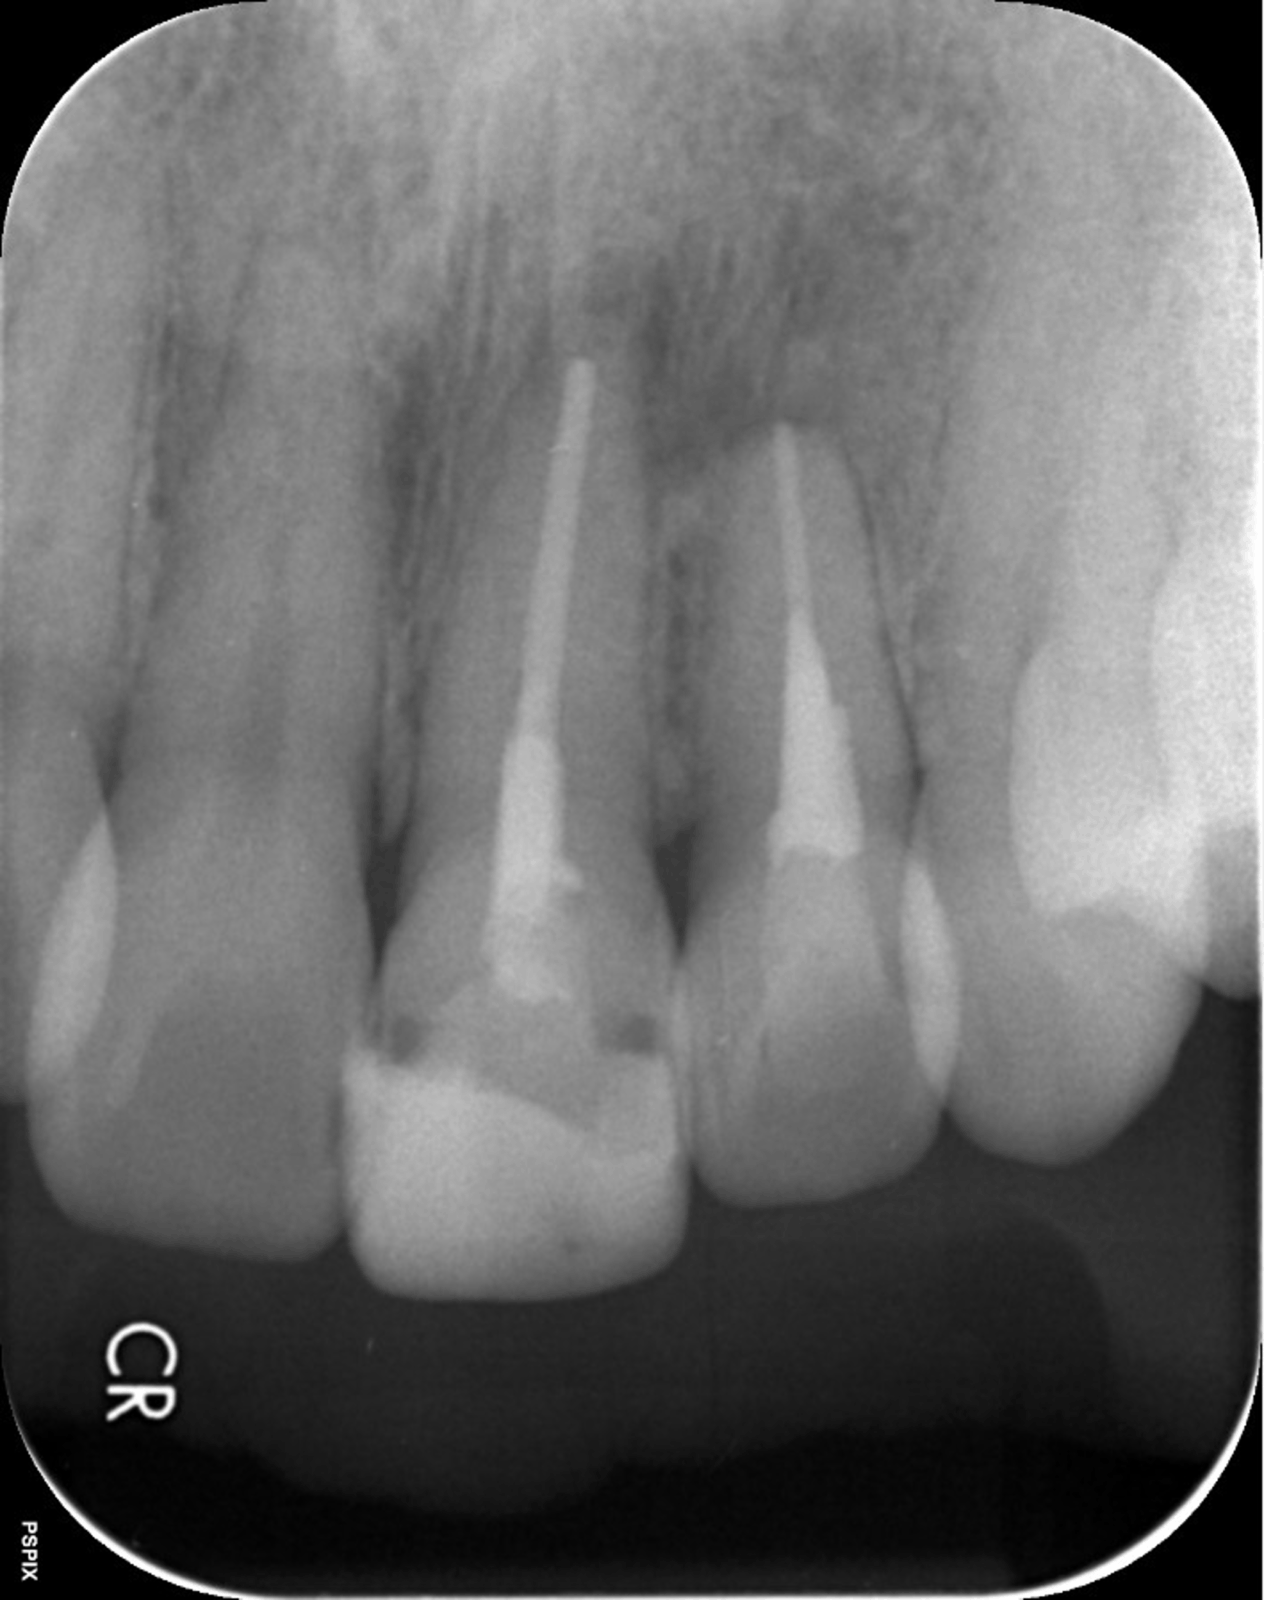

次の画像は、同じ患部をCTとレントゲンで撮影した画像です。

• 比較

「左」の写真がCTで、「右」の画像がレントゲンで撮影したものです。

赤丸で囲んだところには、黒い影が見えます。ここには炎症が起こっているのですが、右の写真には影がありません。つまり、2次元のレントゲンだけで診断した場合、問題のある部分は治療しない選択をするため、最終的には抜歯の運命をたどるケースです。